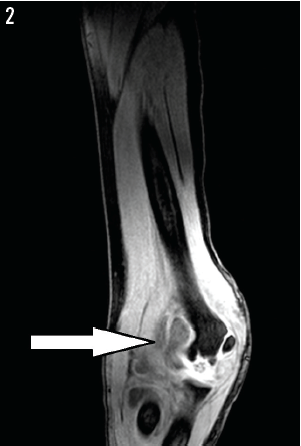

Magnetic resonance imaging of the left elbow revealed humeral osteomyelitis and septic arthritis (Figure 2). The patient underwent another debridement of the left elbow. Wound cultures obtained during the procedure eventually grew Pantoea agglomerans.